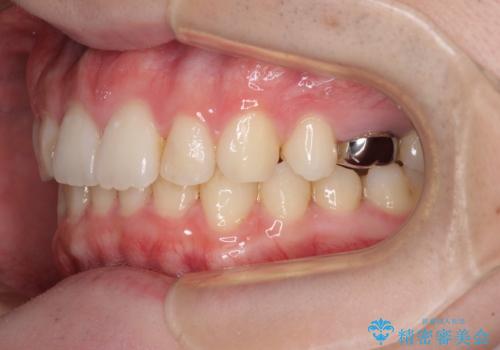

インビザラインによる矯正治療と奥歯のインプラント治療

- 咬み合わせと前歯のデコボコを気にして来院された患者様です。

前から5番目の永久歯が3本欠損しており、乳歯が残存している状態でしたが、インビザラインでも十分に対応可能と判断し、インビザラインにて矯正治療を行うこととしました。

右下の残存している乳歯は萌出しきれておらず、全く咬み合っていない状態であり、インビザラインにて移動できない可能性があるため、ワイヤー矯正の併用も念頭に置いて治療を開始しました。

今回は部分的にワイヤー矯正を用いましたが、右下の乳歯は全く動かなかったため、抜歯をした上でインプラントを埋入し、オールセラミッククラウンにて補綴治療を行いました。